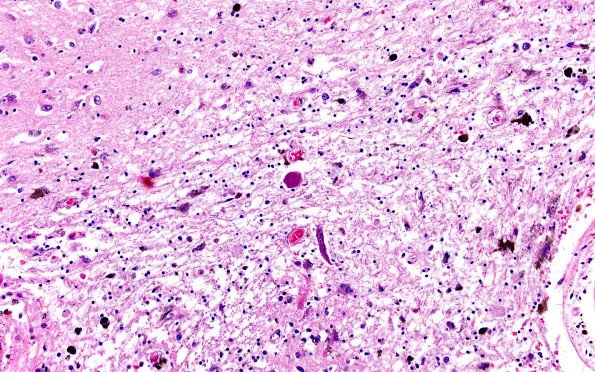

Washington University Experience | VASCULAR | Cavernous Angioma | 31C7 Cavernoma (Case 31) H&E 20X

The adjacent parenchyma consists of free hemosiderin, hemosiderin-laden macrophages, reactive astrocytes, some encrusted by hemosiderin, and granular axonal spheroids. (H&E)